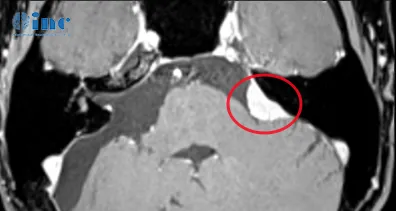

孟女士MR影像

孟女士病情比较特殊,不仅是因为她已经做过一次开颅手术,更是因为她的脑膜瘤长在了CPA桥小脑角区,这是三叉神经、展神经、面神经和听神经等所在之地,并且紧邻脑干延髓、脑桥和小脑。

术前术后影像对比